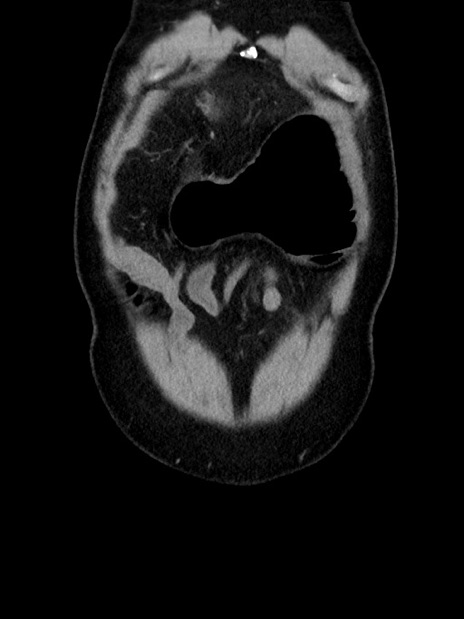

症例35(冠状断像)

横断像